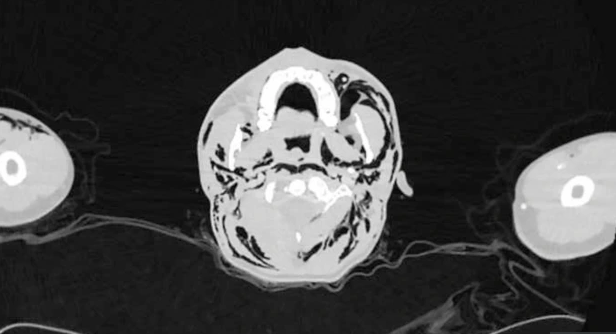

Thăm khám, các bác sĩ phát hiện bệnh nhân bị sưng tấy vùng mặt. Cuối cùng, các bác sĩ phát chẩn đoán nam thanh niên bị chấn thương phổi, thường do những cơn ho hoặc do tập thể dục quá sức.

Bệnh nhân được chẩn đoán mắc chứng tràn khí màng phổi tự phát (SPM). Đây là một tình trạng mà không khí bị rò rỉ từ phổi và đọng lại trong lồng ngực.

Các bác sĩ cho biết không khí bị mắc kẹt đã lan đến hộp sọ của nam thanh niên. Ảnh chụp X-quang cho thấy không khí bị mắc kẹt trong không gian giữa ngực và các túi phổi.